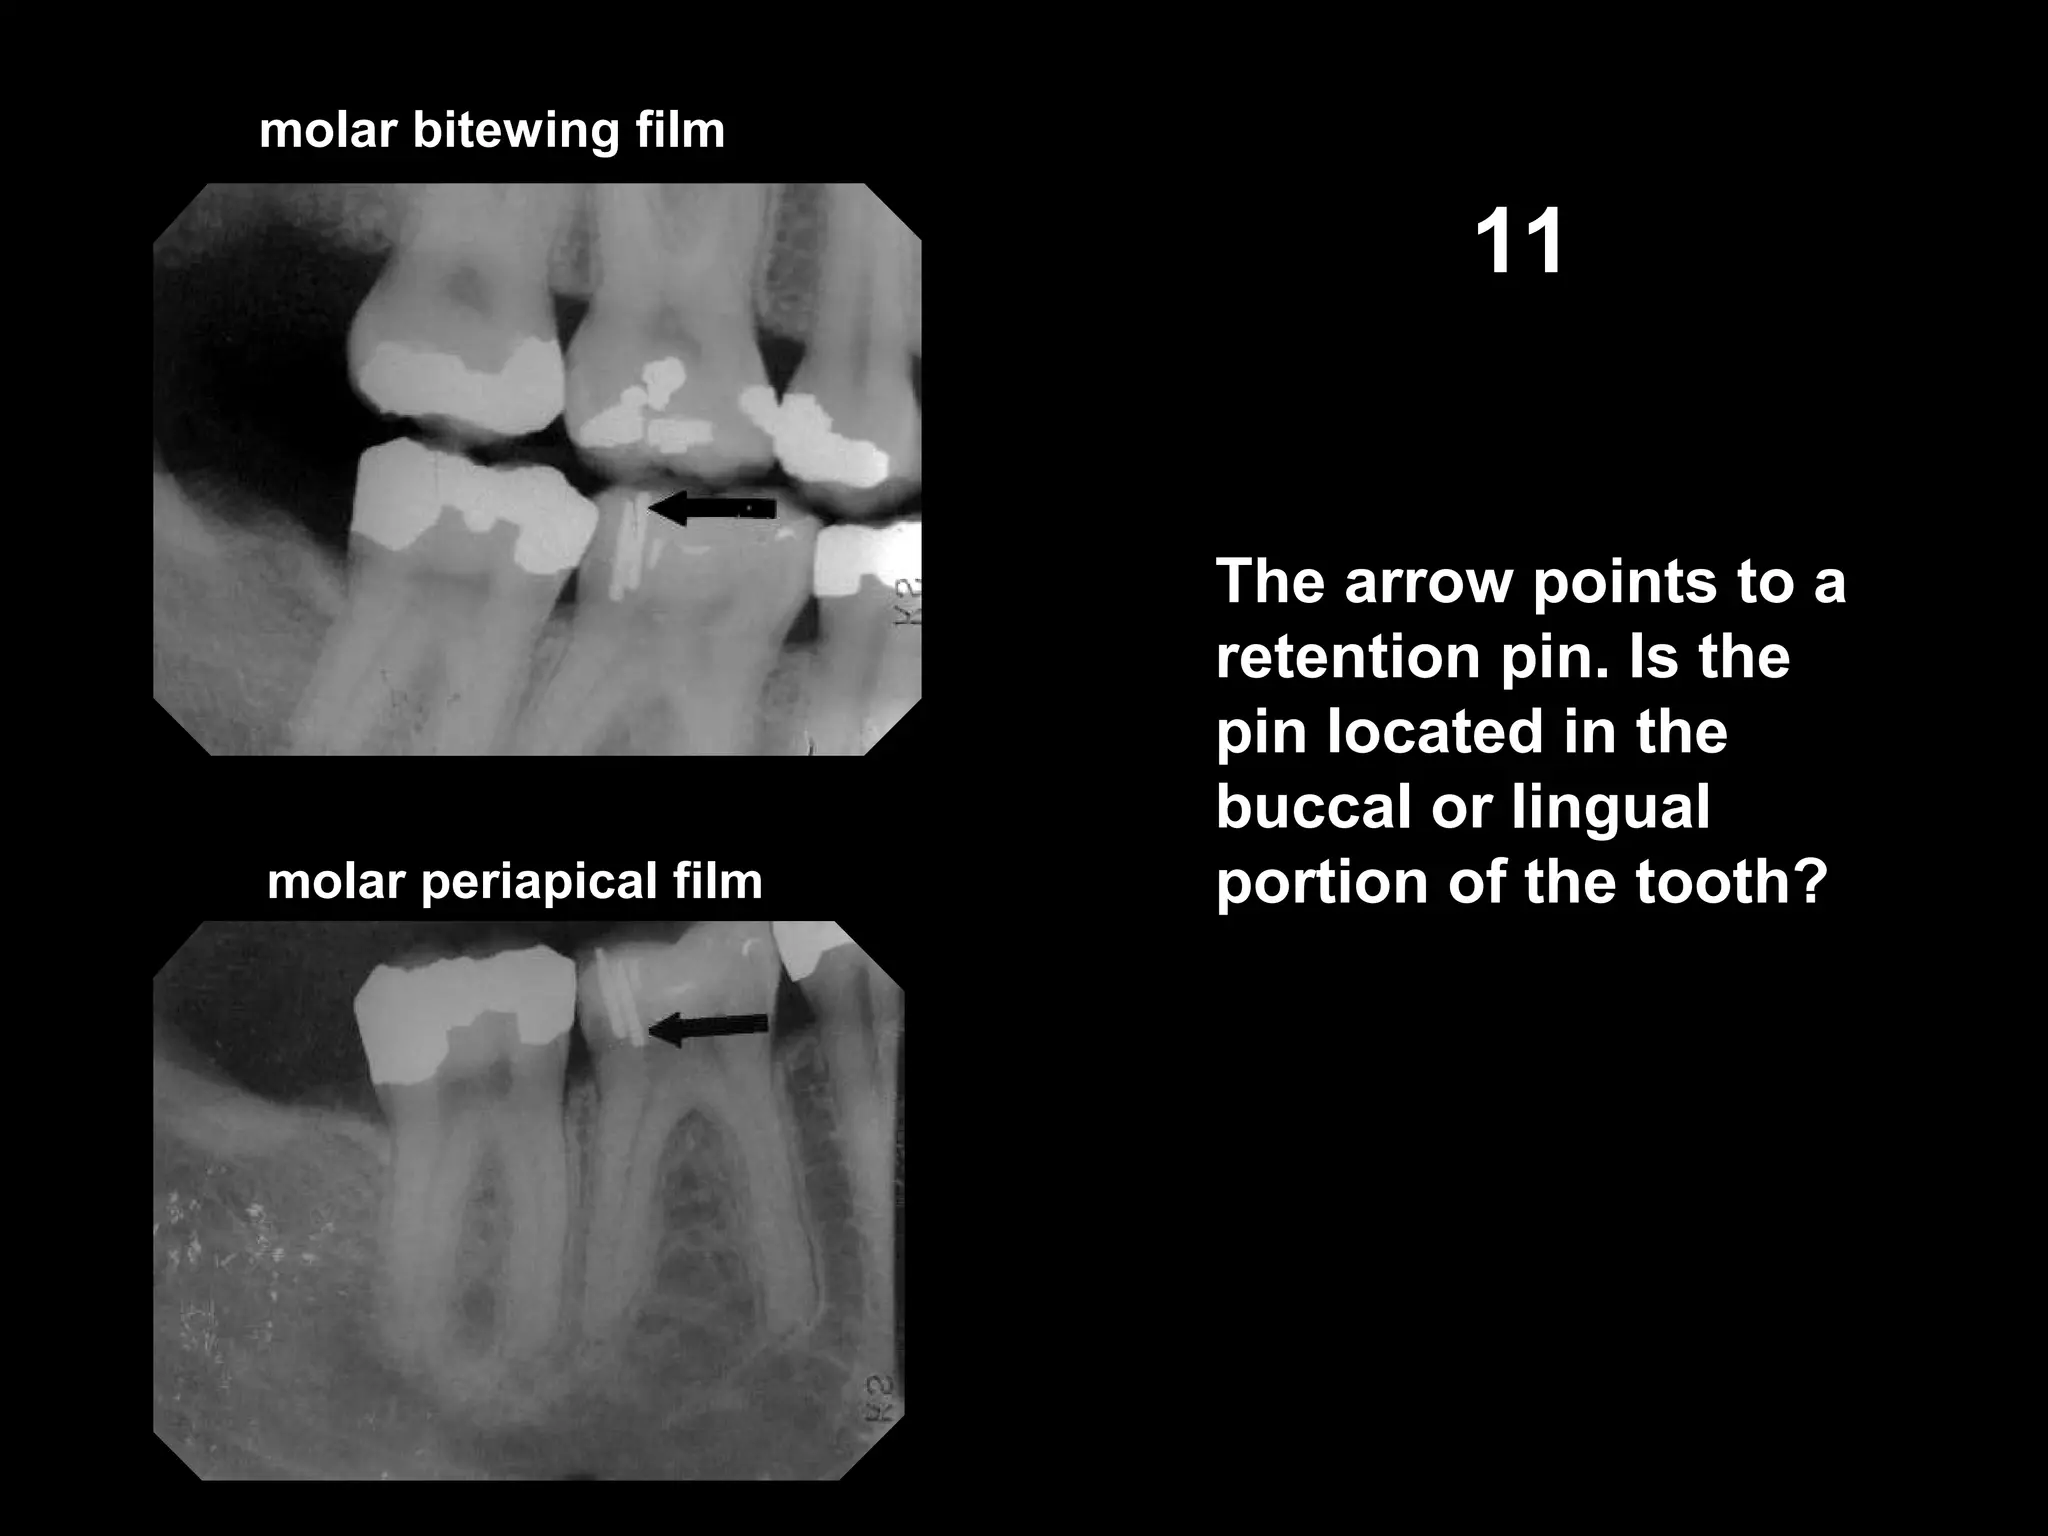

molar bitewing film

molar periapical film

11

The arrow points to a

retention pin. Is the

pin located in the

buccal or lingual

portion of the tooth?